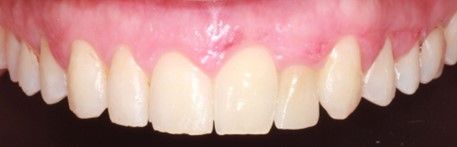

Tras 4 meses de la colocación del implante de circona y la corona provisional (Figura 12), se procedió al escaneado intraoral del muñón para la confección de una corona de circona monolítica.

La corona fue preparada mediante un protocolo adhesivo mecanoquímico18,19, que consistió en el arenado con partículas de óxido de aluminio de 30µm y la aplicación de un adhesivo universal con 10-MDP (Scotchbond Universal, 3M Espe, 3M, Saint Paul, Minnesota, USA). Con seda dental se comprobaron los puntos de contacto y la oclusión fue comprobada con papel de articular de 12 y 8 μm, para asegurar la ausencia de contactos prematuros, así como un correcto contacto anterior. A continuación, se procedió a cementarla mediante un cemento de resina dual (RelyX Unicem 2, 3M Espe, 3M, Saint Paul, Minnesota, USA). Se polimerizó durante 2 segundos con una lámpara de fotopolimerización, se retiraron los excesos mediante hilo dental y sonda, procediéndose a fotopolimerizar durante 40 segundos más en cada cara de la corona. El paciente expresó su satisfacción con el tratamiento a nivel estético y funcional, con un seguimiento clínico de 12 meses (Figura 13).